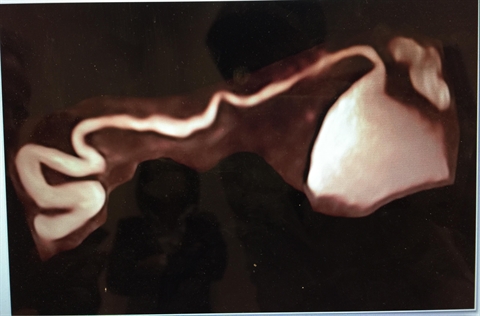

| Visualisation de la trompe en 3D par la technique Hyfosy. |

Bruno Schaub partage ses expériences sur la technique «Hyfosy», une nouvelle pratique encore jamais utilisée au Vietnam. Cette technique échographique permet d’étudier la perméabilité tubaire. C’est une technique plus simple, plus rapide et moins couteuse que l’hystérosalpingographie.